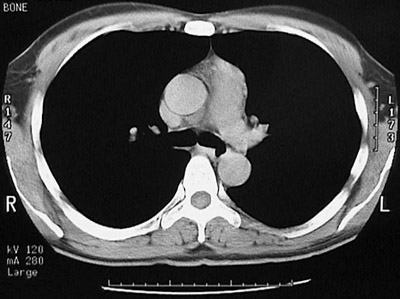

Click on the thymoma in the the chest CT scan above:

Here is a thymoma of the anterior mediastinum seen with this chest CT scan. It is in the anterior mediastinum arising in the left aspect of the thymus anterior and to the left of the aortic arch.